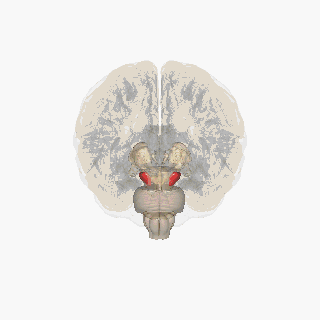

Substantia nigra

Substantia nigra highlighted in red.

Coronal slices of human brain showing the basal ganglia, globus pallidus: external segment (GPe), subthalamic nucleus (STN), globus pallidus: internal segment (GPi), and substantia nigra (SN, red). The right section is the deeper one, closer to the back of the head